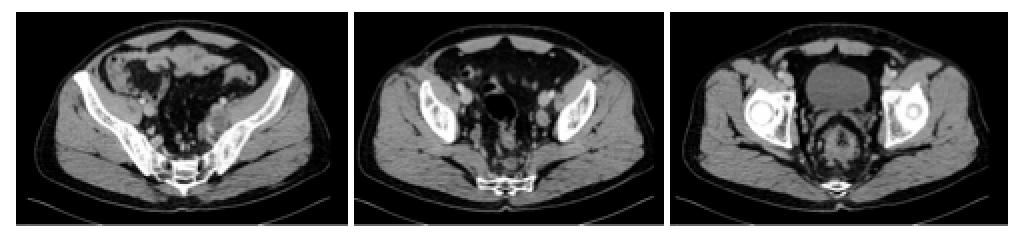

全腹CT

直肠中下段肠壁增厚,考虑直肠癌,伴直肠周围间隙、直肠旁间隙、双侧髂血管旁淋巴结增多、增大,请结合临床及其他检查。

左侧肾上腺结节,转移?腺瘤?或其他?左肾前下份轮廓欠光整,慢性炎症改变?左肾小囊肿。

肝右后叶上段钙化灶

疗效评估(同步放化疗结束时,2017.2.14):SD

直肠中下段肠壁增厚,考虑直肠癌,伴直肠周围间隙、直肠旁间隙、双侧髂血管旁淋巴结增多、增大,与2016-12-2日旧片比较,左侧髂血管旁淋巴结略缩小,其余未见明显变化,请结合临床及其他检查。

左侧肾上腺结节,转移?腺瘤?或其他?与上述旧片比较未见明显变化。

左肾前下份轮廓欠光整,慢性炎症改变?左肾小囊肿。

肝右后叶上段钙化灶。

前列腺钙化灶。

疗效评估(2017.4.26):PR?

直肠中下段肠壁增厚,考虑直肠癌,伴直肠周围间隙、直肠旁间隙、双侧髂血管旁淋巴结增多、增大,与2017-02-14日旧片比较,直肠壁增厚较前减轻,其余未见明显变化,请结合临床及其他检查。

腹部CT

“直肠癌术后”,未见明显复发征象,请结合临床及其他检查。

腹盆腔少许积液,盆底筋膜增厚。双侧盆壁内侧斑片状及片状不规则低密度影,未见明显强化,积液可能,请随访。

左侧肾上腺结节,转移?腺瘤?或其他?与2017-04-26旧片比较未见明显变化。

左肾前下份轮廓欠光整,慢性炎症改变?

左肾小囊肿。